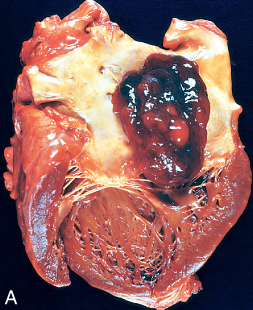

myxoma

the left atria– atria fibrillation atrial thrombi (stroke)